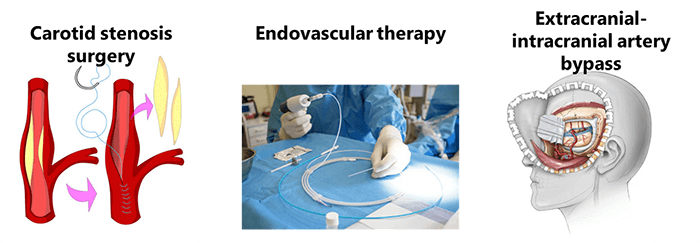

A variety of techniques have been adopted for treatment:

- Carotid stenosis surgery

- Endovascular therapy

- And extracranial intracranial artery bypass